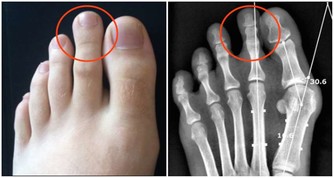

雖然科學還不能提供人類大腦結構變化的確切證據,但按照他的假設,大腦的功能在過去20年間的改變,很可能比過去數千年的變化更大。數字技術對於大腦進化的意義,可以與30萬年前人類祖先第一次學會使用工具相提並論—— 工具的使用導致了大腦額葉與前額葉皮層區的急劇變化,從而促進了語言與社交功能的進化。

他做過一個實驗,研究經常上網的人和從未上網的人的大腦在使用搜索引擎和讀書時的不同反應。結果發現,當閱讀書面文字時,上網高手與上網生手沒有表現出任何區別。而當在Google上搜索時,兩組實驗對象的大腦神經激活表現則明顯不同——上網高手在大腦左前區的一個特定網絡,即被稱為背外側前額葉皮層的區域(其功能是控制我們的決策和整合複雜信息的能力)很活躍,而上網生手的大腦在這一區域的活動甚微。但是,在互聯網上僅活動5天之後(每天1小時),Google就在他們的大腦中激活了這一區域。